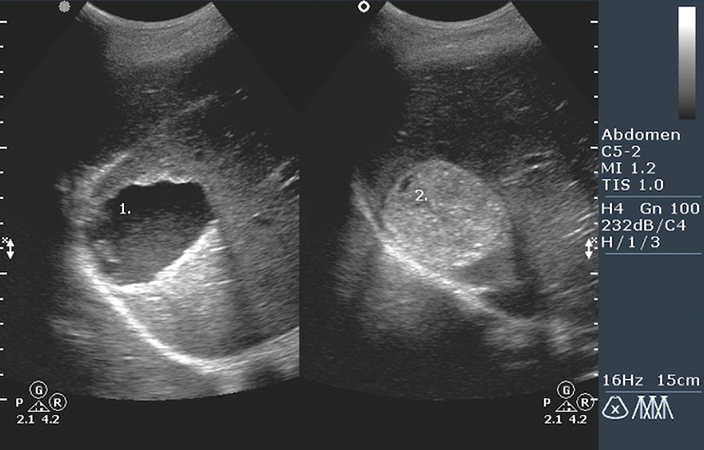

Методы обследования пациента с использованием инструментов включают в себя:

- Ультразвуковое исследование (УЗИ) – используется для обнаружения различных образований, определения их численности и размеров.